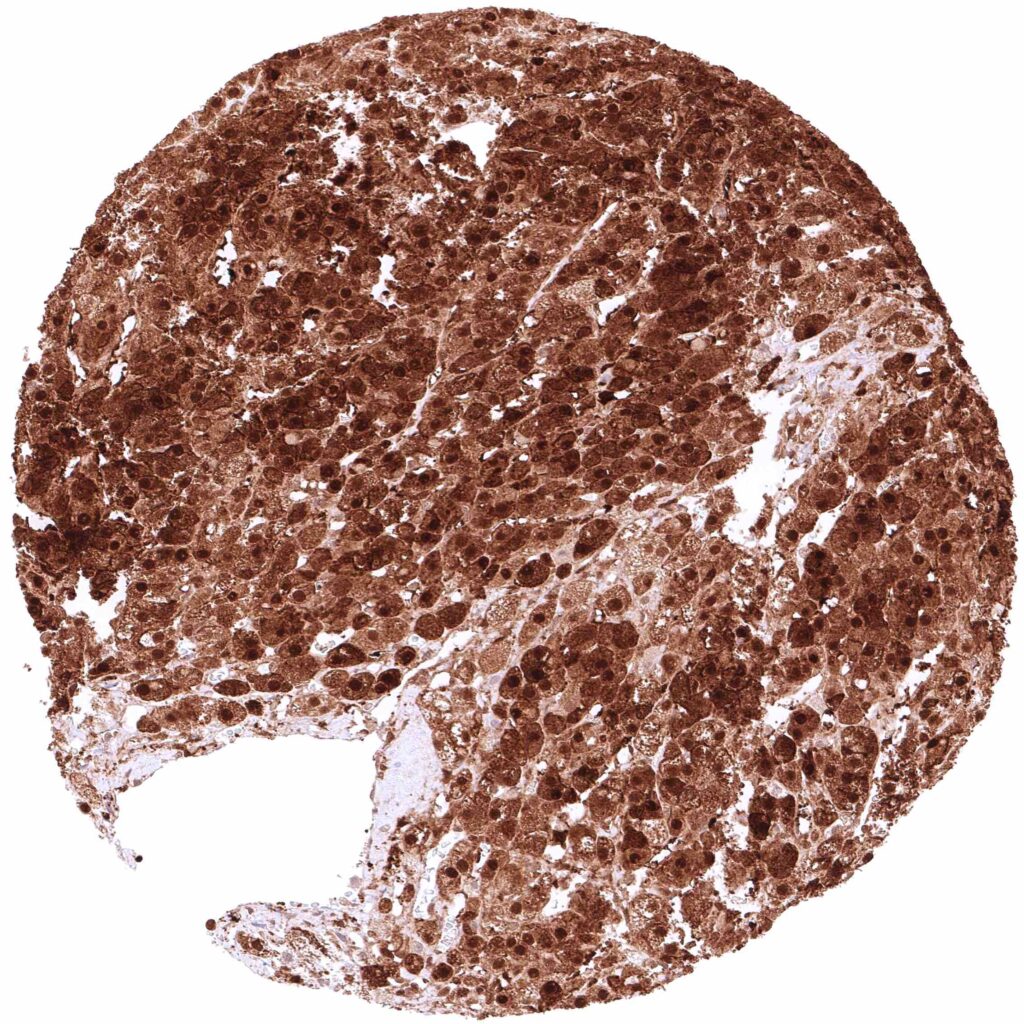

Spleen – At least a weak cytoplasmic GSTP1 positivity occurs in all cells of this sample.